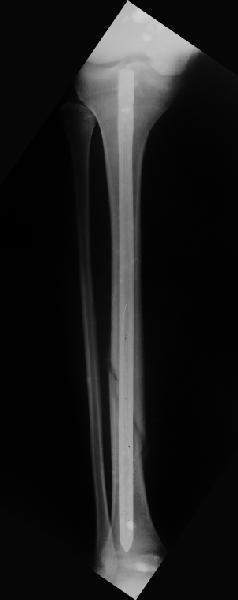

Вчера первый раз синтезировали голень гвоздем Fixion.

Спиральный оскольчатый перелом, ниже середины, у молодого парня. Сделали "классический" вариант гвоздя, который еще без винтов. Получилось все легко. Не торопясь, сделали операцию минут за 20. См. фото.